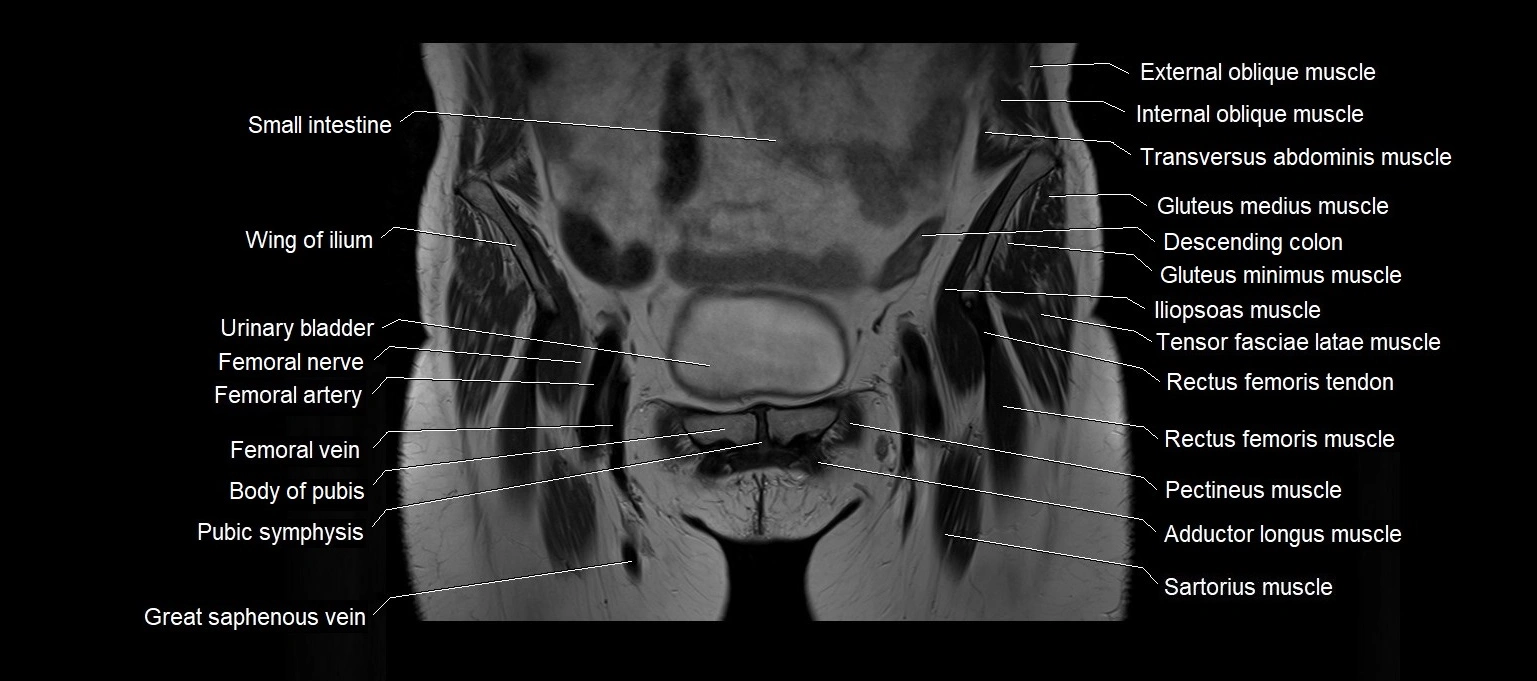

MRI images